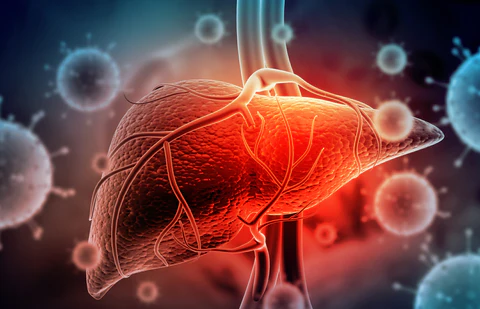

AAFQ™ Polygonum Multiflorum and Ginseng Extract Herbal Spray is specifically formulated to address conditions such as fatty liver, alcoholic hepatitis, liver fibrosis, obesity, insomnia, cirrhosis, hair loss, jaundice, gallbladder disease, and liver dysfunction. Our formula is designed to provide powerful liver support through sublingual absorption, activating liver cell regeneration, repairing the liver, enhancing detoxification capabilities, reducing inflammation, and decreasing visceral fat. By using our spray, you can expect increased energy and vitality within 8 weeks, helping you regain robust liver detoxification function.

AAFQ™ Polygonum Multiflorum and Ginseng Extract Herbal Spray is specifically formulated to address conditions such as fatty liver, alcoholic hepatitis, liver fibrosis, obesity, insomnia, cirrhosis, hair loss, jaundice, gallbladder disease, and liver dysfunction. Our formula is designed to provide powerful liver support through sublingual absorption, activating liver cell regeneration, repairing the liver, enhancing detoxification capabilities, reducing inflammation, and decreasing visceral fat. By using our spray, you can expect increased energy and vitality within 8 weeks, helping you regain robust liver detoxification function.

AAFQ™ Polygonum Multiflorum and Ginseng Extract Herbal Spray” is designed for sublingual absorption, allowing its ingredients to act on the liver through the bloodstream. It stimulates rapid regeneration of liver cells and enhances detoxification effects, providing liver support within one day and promoting liver health restoration. AAFQ™ research team has pioneered an efficient extraction technique that combines active components from various herbs, enabling you to achieve a healthy liver within four weeks.